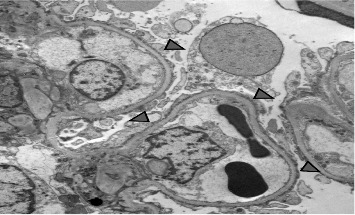

Proteinuria in a patient with long-standing Type 1 diabetes mellitus (T1DM) usually suggests diabetic kidney disease (DKD). However, DKD occurs late in the disease and is associated with hypertension and retinopathy. We report an adolescent with T1DM who, 1 year after initial diagnosis, developed nephrotic syndrome (NS). He was treated with steroids but developed frequent relapses and became steroid-dependent. A subsequent kidney biopsy revealed minimal change disease (MCD) and mild DKD. He was treated with mycophenolate mofetil (MMF) and remains in remission. Primary podocytopathy, such as MCD, is a rare cause of NS in a patient with T1DM. Indications for kidney biopsy and treatment options are similar to those of other children with a diagnosis of NS. This report highlights that, although rare, primary glomerulopathy can occur in pediatric diabetic patients and should be considered in the differential diagnosis of proteinuria, as early recognition and intervention can lead to favorable outcomes.

Abstract Image